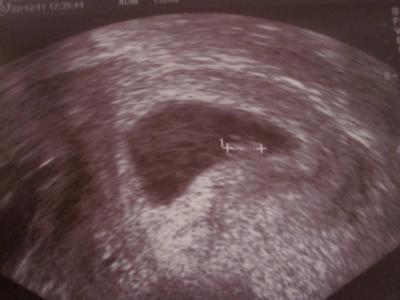

Halli - Hallo! Hatte ja gestern auch angekündigt, heute Abend meinen Gyn-Termin zu haben. Mein Mann war erstmals mit - und wir haben unseren kleinen Zwerg wieder gesehen! Heute knapp 9 mm "groß", das Herzchen schlug weiterhin kräftig und im Doppler konnte man alles wunderbar durchblutet erkennen! Und hier für Euch das US Bild - mein Mann war völlig fassungslos! Ach so - wir sind heute ganz genau bei 6+5!

Bild zu Zurück vom Doc! - Forum für August - Mamis